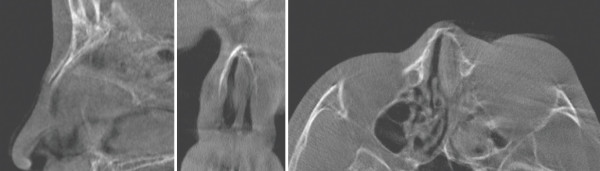

5b20f0b2d5a7f90b24c2bdfd0ae62eeb_1773279369_4318.jpg

CT상 비골의 복합 골절이 관찰된다. 측면에서는 비골의 함몰, 정면과 밑면에서는 비골의 좌측 이동과 동반된 비중격의 골절을 확인할 수 있다. 이러한 비골과 비중격 골절을 방치한다면 안장코 변형과 코막힘을 초래할 수 있다.